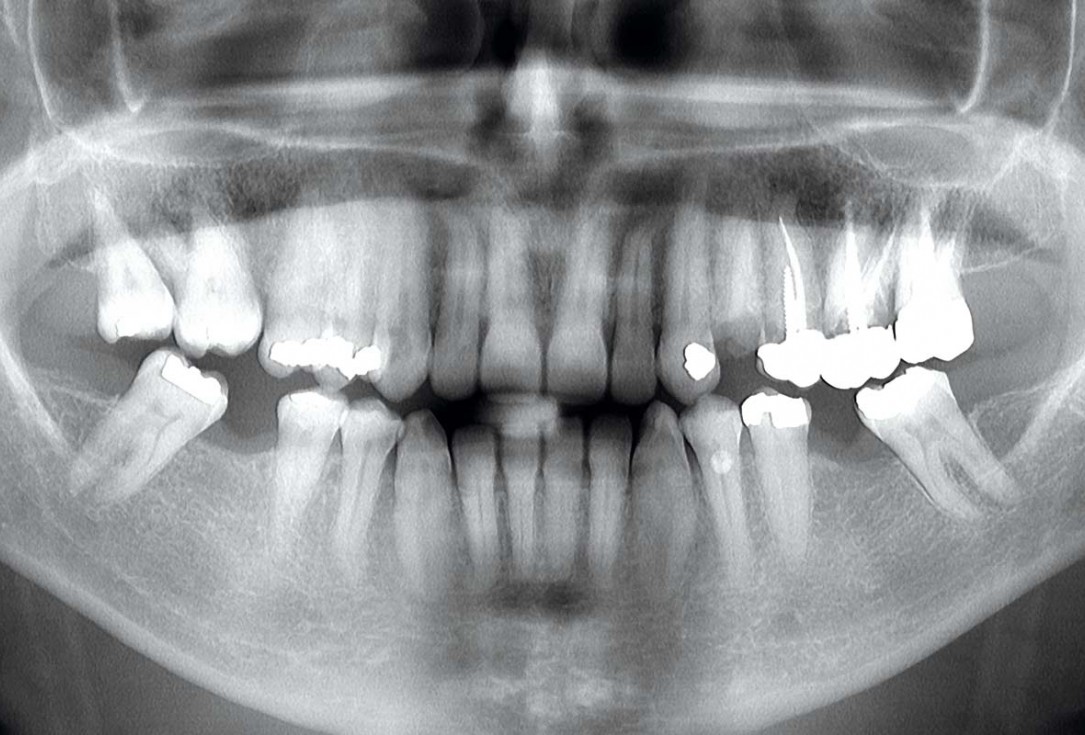

1/13 - Pre-operative OPG, teeth 24, 25, and 26 planned for extraction